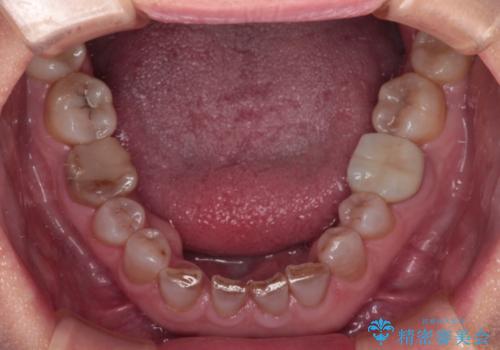

- 前歯の変色や欠損による隙間を気にして来院された患者様です。

上顎前歯は樹脂による変色を覆い隠す処置が行われていましたが、汚れが溜まりやすく厚みも増している状態でした。

上顎前歯は樹脂を外し、下顎前歯の隙間はそれぞれの歯を大きくするように補綴治療を行うことで隙間を埋めることとしました。